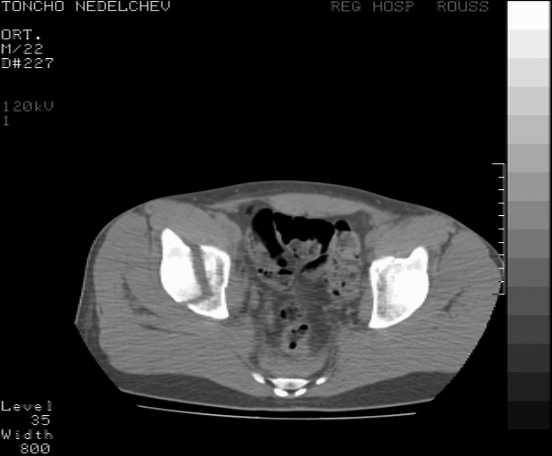

Re: Acetabular fracture

Here are some more axial images. What is your opinion as for the timing of the operative treatment?